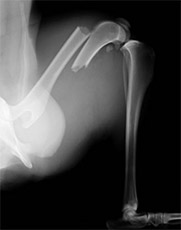

前肢上腕骨骨折

このタイプの骨折は猫、特に外に行く猫ちゃんに多く、高い所から飛び降りて着地に失敗することで骨折することが多いです。

手術前

手術後

この箇所の骨折は筋肉が多く、強度の高い固定が必要です。また今回みたいな斜骨折が多く認められます。髄内ピン、スクリュー、ワイヤーで治療を行いました。